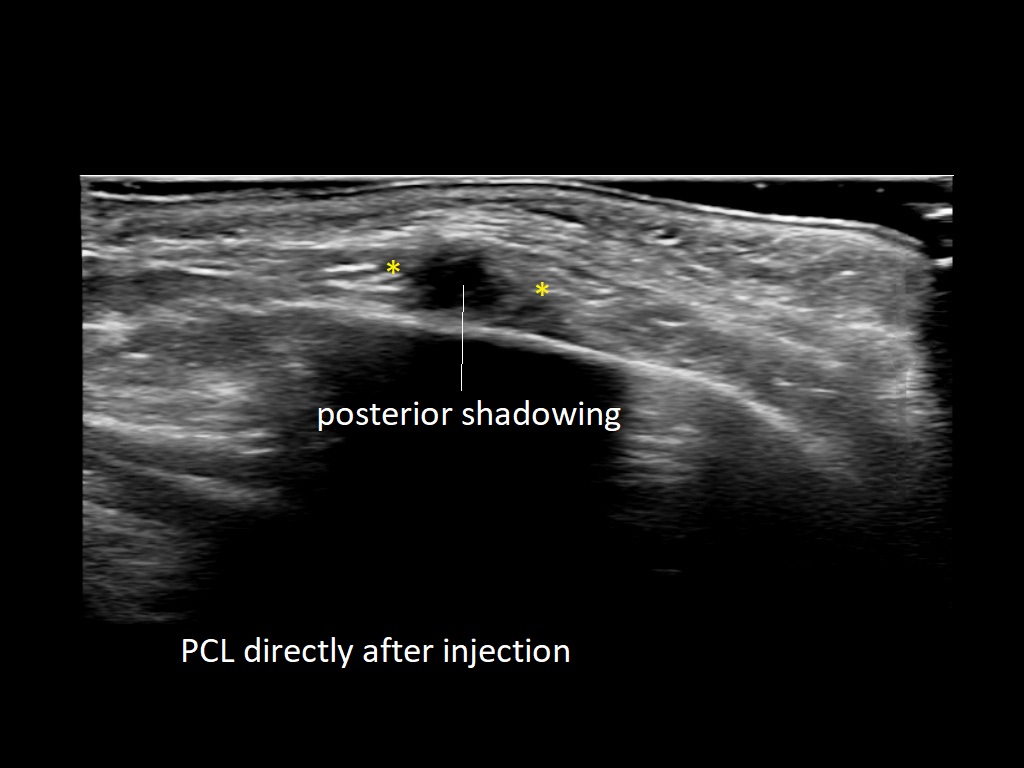

PCL 0

PCL 10a

PCL 11a

PCL 12a

PCL 13a

PCL 14a

PCL 15a

PCL 16a

PCL 1a

PCL 2a

PCL 3a

PCL 3b e

PCL 4a

PCL 4b e

PCL 5a

PCL 5b e